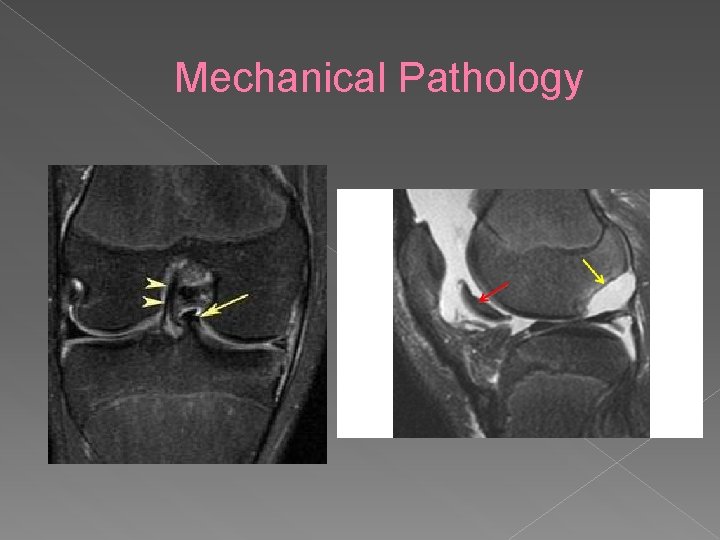

Mechanical Pathology